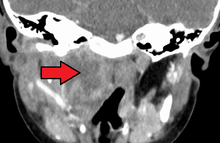

| A lateral cervical spine x-ray demonstrating prevertebral soft tissue swelling (marked by the arrow) as seen in a person with a retropharyngeal abscess. | |

A computed tomography (CT) scan is the definitive diagnostic imaging test.[4]

X-ray of the neck often (80% of the time) shows swelling of the retropharyngeal space in affected individuals. If the retropharyngeal space is more than half of the size of the C2 vertebra, it may indicate retropharyngeal abscess.[5]